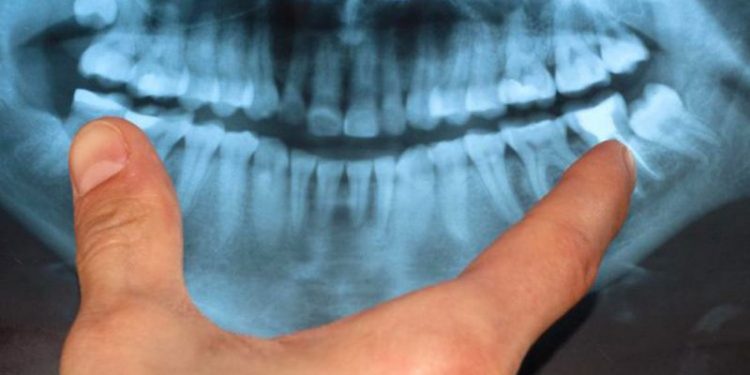

Ndikimi i Problemeve të Dhëmbëve tek Shëndeti i Zemrës. Të gjithë ekspertët e shëndetit tregojnë se ekziston një lidhje mes shëndetit të gojës dhe atij të zemrës.

Gjithsesi, shumë studime të mëvonshme të konsultuara nga AgroWeb.org tregojnë një lidhje konkrete mes periodontozës (sëmundje e mishrave të dhëmbëve) dhe sëmundjeve të tjera, përfshirë këtu dhe problemet serioze të zemrës.

Kërkimet sugjerojnë se periodontoza shoqërohet me një rritje të rrezikut ndaj sëmundjeve kardio-vaskulare.

Njerëzit me sëmundje kronike të mishrave të dhëmbëve, raporton AgroWeb.org, vuajnë gjithashtu nga një ngushtim i venave të gjakut që ndodhen në qafë, të cilat ndikojnë direkt në zemër.